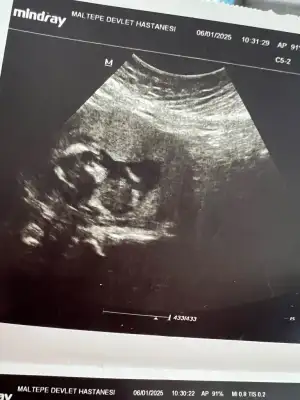

Selam herkese 15. Hafta kontrolümden çıkan ultrason görüntüsünü atıyorum ben baya bebek şekli görebiliyorum gibi geliyor sizce de öyle mi 😃 aynı yiğenime benziyor hatta 😃🧿🙏

DR. Demir hapı verdi ve 1 ay sonra detaylı ultrason için gel dedi.

Bu arada istanbul maltepeye taşındım bugünlük devlet hastanesinde gülüzar diye bi doktora gittim fena değildi ama bilemedim dr tavsiyesi olan varsa buralarda dinliyorum. ❤️🥰🧿🙏